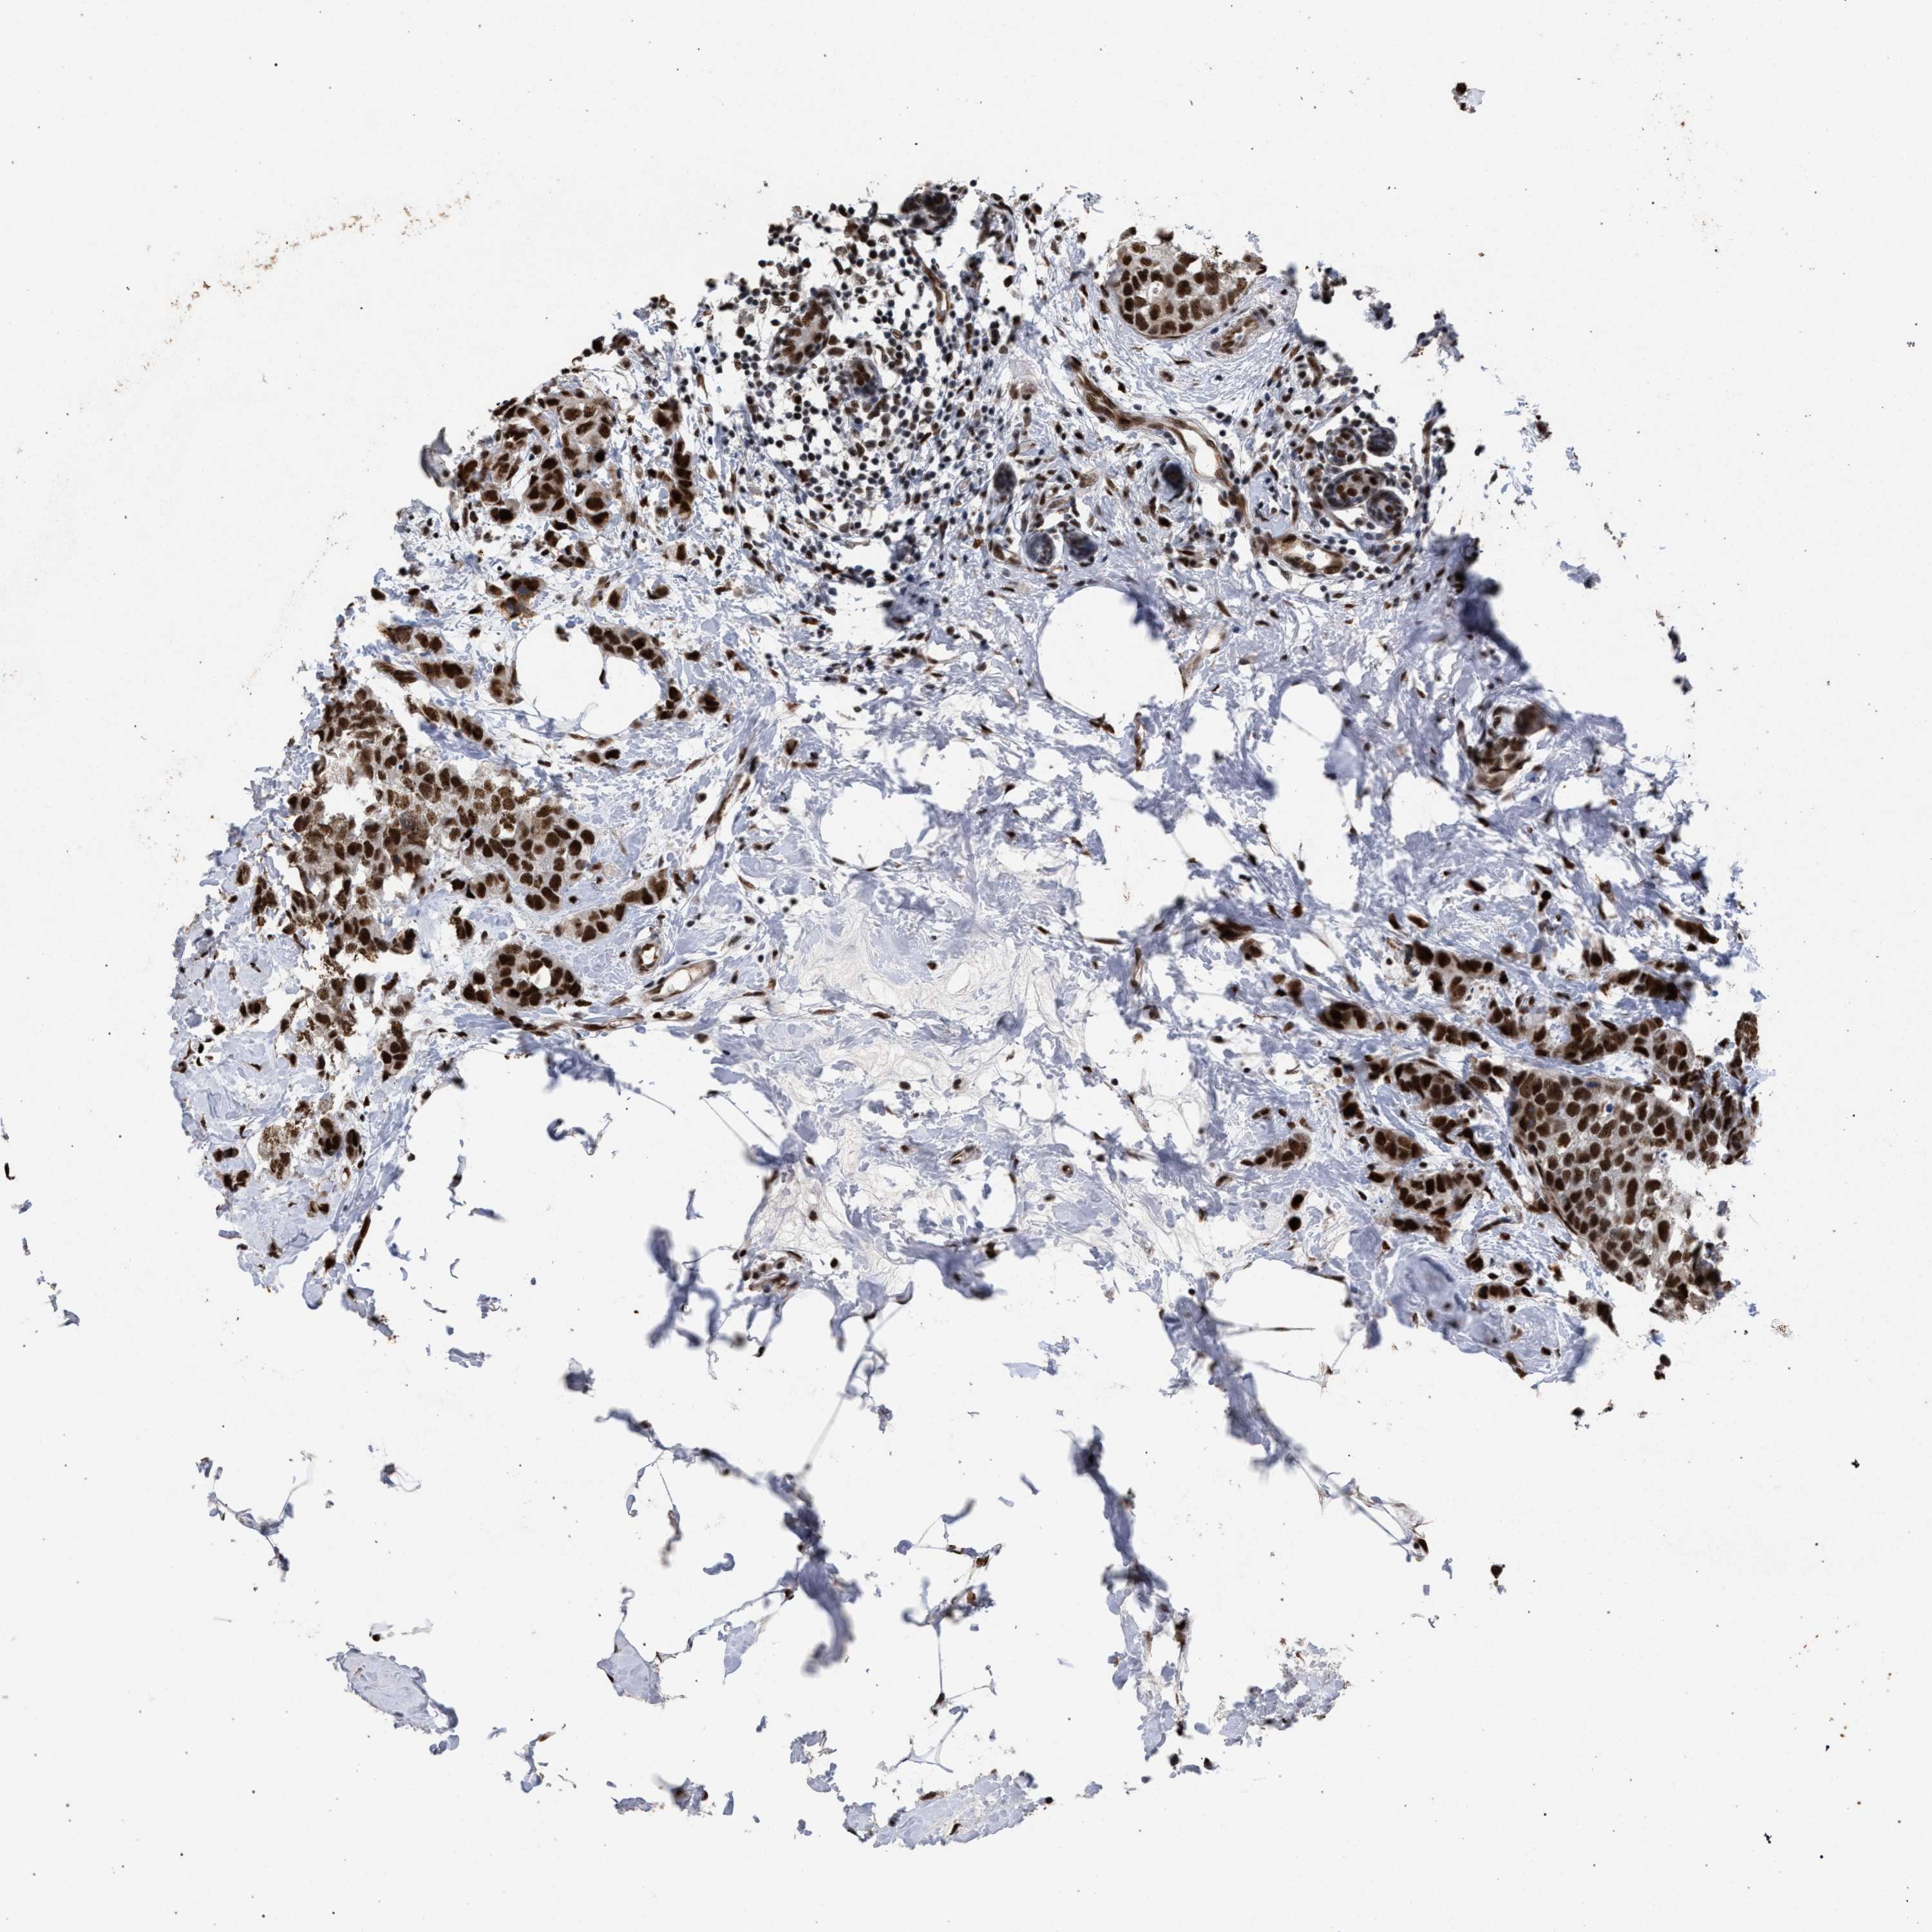

BRCA TCGA BRCA VALIDATION PROTEIN EXPRESSION